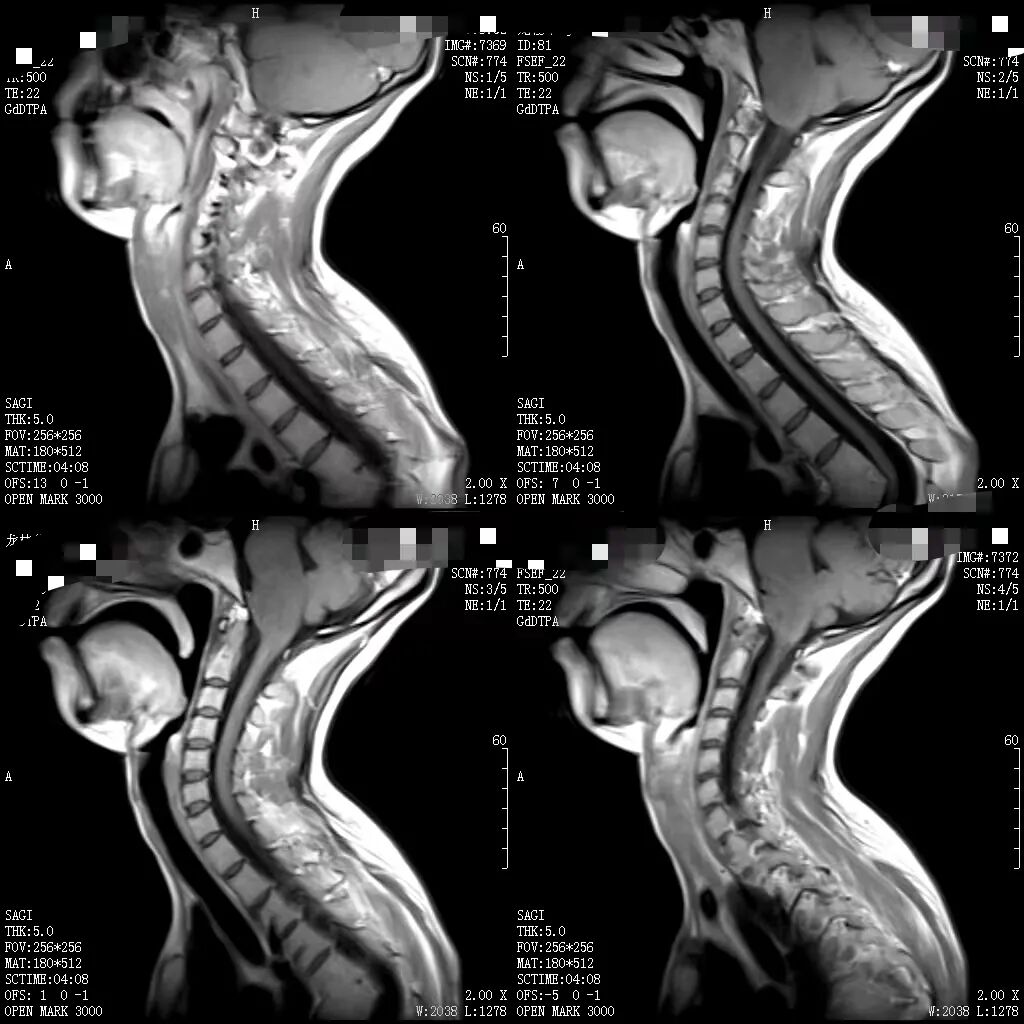

随着医学科学技术的快速发展,磁共振成像(MRI)检查作为一种非侵入性、高分辨率的成像技术,具有广泛的应用范围,已经成为临床诊断中不可或缺的工具。

何军主任以深厚的医学造诣和前瞻性视野,从MRI的基本原理讲起,深入浅出地剖析了磁共振成像的奥秘,检查方法,各类适应症,禁忌症以及最新技术应用等。从理论要点到临床应用,从经典案例到前沿技术,无一不娓娓道来,深刻阐述了MRI技术对于现代临床工作的重大意义。他强调:“MRI以其无创、多参数、高分辨率等独特优势,在中枢神经系统、心血管系统、骨关节及肌肉系统、颈部、腹部、盆腔等病变的诊断中展现出无可替代的价值,希望参与本次培训的医师们能够从中受益,学以致用。”